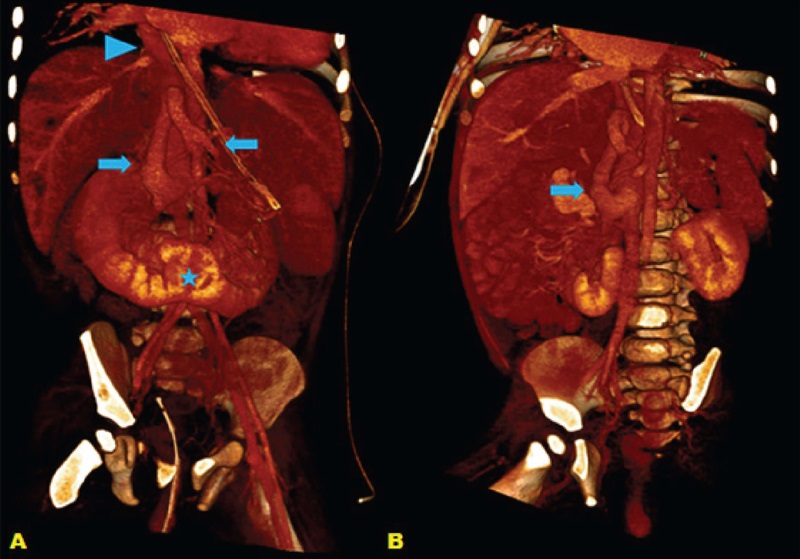

In the postoperative period, due to the persistence of cyanosis, further investigation and imaging study were indicated, which:

Showed medialized liver and absence of inferior vena cava (IVC) intrahepatic segment. Infrahepatic portion continuing with the azygos system at the thoracic cavity level (Figure 3). Also, ectasia of the splenomesenteric venous circulation, and hepatic and superior mesenteric arteries, polysplenia, and intestinal malrotation (Figures 4 and 5).

Not identifed the portal vein inferring agenesis, with mesenteric-caval communication at renal venous drainage level, as shown in Figure 3. There were signs suggestive of hepatic peribiliary fibrosis (at the expense of focal intrahepatic bile duct ectasia) and moderate ascites, typical findings related to Abernethy type I malformation.